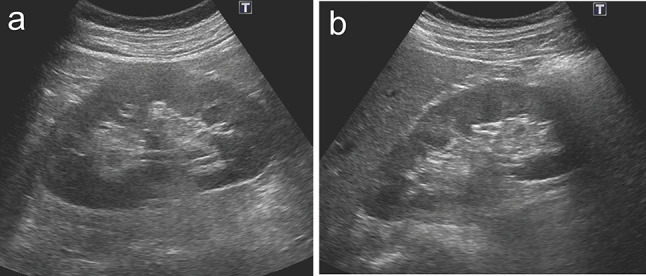

Membranous nephropathy (MN) is a common cause of adult-onset nephrotic syndrome. It is also known as a minor but established renal manifestation of Immunoglobulin G4-related disease (IgG4-RD). Previous reports suggest that MN can also be an initial manifestation of IgG4-RD, all of which are phospholipase A2 receptor (PLA2R)-negative MN. We describe a case of PLA2R-positive MN that subsequently developed other manifestations of IgG4-RD. A 60-year-old male with nephrotic syndrome was diagnosed as primary MN with positive staining for PLA2R on the initial renal biopsy, which remained in partial remission with supportive therapy using angiotensin II receptor blocker (ARB) without steroid. About 1 year later, a renal mass was detected during an annual checkup, and contrast-enhanced computed tomography revealed low-density masses in bilateral kidneys and the head of the pancreas. The findings of endoscopic biopsy of the pancreatic mass were consistent with autoimmune pancreatitis (AIP) and the second renal biopsy showed the findings of MN with tubulointerstitial nephritis, both of which led to a diagnosis of IgG4-RD. The second renal biopsy also showed positive PLA2R. The patient received oral glucocorticoid therapy for IgG4-RD, which improved IgG4-related AIP and renal masses and also resulted in complete remission of MN. To our knowledge, this is the first reported case of PLA2R-positive MN with subsequent development of IgG4-RD. It is sometimes difficult to determine whether PLA2R-positive MN occurring with IgG4-RD is primary MN or secondary MN associated with IgG4-RD. The possibility of developing IgG4-RD should be considered even when preceding MN is PLA2R-positive, suggesting of primary MN.